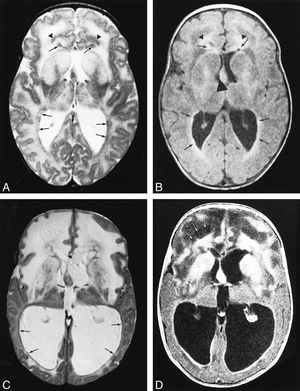

Diagnosis?(Brain MRI)

Hydrocephalus the ventricles are very enlarged